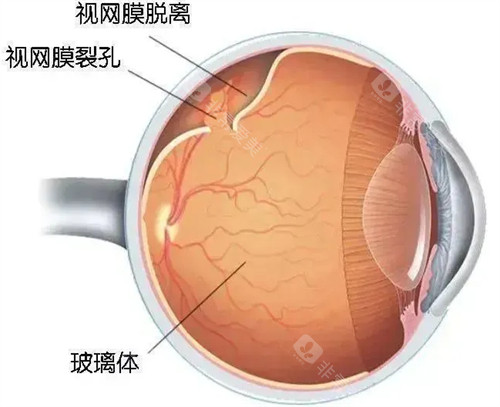

作为首都医学大学附属北京同仁医院眼底病科的“定海神针”,他擅长复杂眼底病诊疗,尤其对视网膜脱离、糖尿病视网膜病变等疾病的手术处理堪称业内标杆。